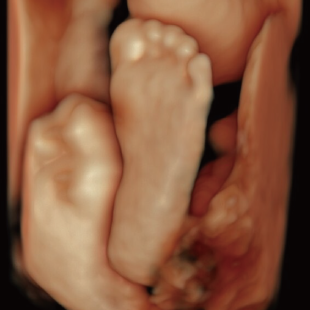

Voluson Expert 22®(GEHealthcare)という産婦人科領域におけるハイエンド超音波診断装置を使用しています。 従来機種と比べ、より高精細な画像描出性能と高度な解析機能を備えており、 胎児の発育や形態をより詳細に観察することが可能です。